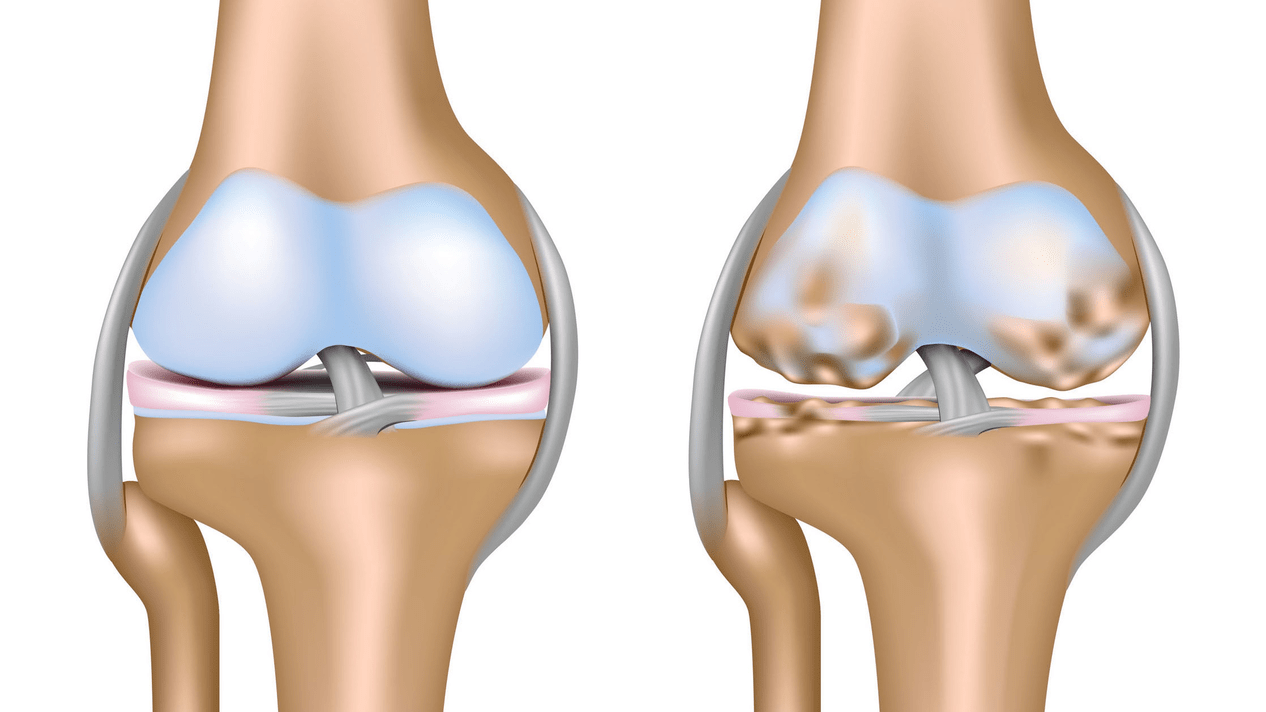

Arthrose des Kniegelenks (Gonarthrose) ist eine chronisch fortschreitende Erkrankung der Kniegelenke mit Schädigung, Ausdünnung und Zerstörung ihres knorpeligen Teils (Gelenkflächen von Femur und Schienbein) sowie Schädigung des subchondralen Knochens. Durch Untersuchungen (Arthroskopie und Magnetresonanztomographie) konnte gezeigt werden, dass neben der Schädigung des Gelenkknorpels auch die Menisken und die Gelenkinnenhaut an dem Prozess beteiligt sind. Gonarthrose ist eine der häufigsten orthopädischen Erkrankungen. Es gibt seine Synonyme: Arthrose (OA), deformierende Arthrose. Die Krankheit stellt ein wichtiges sozioökonomisches Problem dar, da sie weit verbreitet ist und aufgrund ständiger Schmerzen die Lebensqualität der Patienten erheblich verschlechtert und darüber hinaus zu großer Behinderung führt.

Bis Mitte der achtziger Jahre des letzten Jahrhunderts gab es keine einheitliche Definition der Krankheit. Erst 1995 charakterisierte das Osteoarthritis-Komitee des American College of Rheumatology die Krankheit als Folge mechanischer und biologischer Faktoren, die zu einem Ungleichgewicht zwischen den Abbau- und Syntheseprozessen der extrazellulären Matrix des Gelenkknorpels führen. Dadurch kommt es zum Zerfall und zur Degeneration der Fasern, es kommt zu Rissen, Osteosklerose und Verdichtung der kortikalen Schicht des subchondralen Knochens, es wachsen Osteophyten und es bilden sich subchondrale Zysten.

Bei der Arthrose (Osteoarthrose) kommt es neben der fortschreitenden Zerstörung des Knorpels, dem Verlust seiner Elastizität und stoßdämpfenden Eigenschaften auch zu einer allmählichen Beteiligung der Knochen an dem Prozess. Unter Belastung entstehen scharfe Kanten (Exostosen), die fälschlicherweise für „Salzablagerungen“ gehalten werden; Bei der klassischen Arthrose kommt es nicht zu Salzablagerungen. Mit fortschreitender Arthrose „frisst“ sie den Knorpel weiter auf. Dann verformt sich der Knochen, es bilden sich dort Zysten, alle Gelenkstrukturen sind betroffen und das Bein beugt sich.

Das erste Stadium der Erkrankung ist durch primäre Veränderungen des hyaliner Knorpels gekennzeichnet. Knochenstrukturen werden nicht beeinträchtigt. Die Blutversorgung in intraossären Gefäßen und Kapillaren ist gestört. Die Knorpeloberfläche trocknet aus und verliert ihre Glätte. Geht die Erkrankung mit einer ständig angespannten Synovitis einher, entsteht eine Baker-Zyste (Hernienvorwölbung der Gelenkkapsel der Kniekehlenregion). Nach starker Belastung des Gelenks kommt es zu einem dumpfen Schmerz. Es kann zu einer leichten Schwellung kommen, die nach Ruhe verschwindet. Es gibt keine Verformung.

Gonarthrose, Stadium II

Im zweiten Stadium wird die Knorpelschicht deutlich dünner und verschwindet an manchen Stellen ganz. An den Rändern der Gelenkflächen treten Osteophyten auf. Die qualitativen und quantitativen Eigenschaften der Gelenkflüssigkeit verändern sich: Sie wird dicker und zähflüssiger, was zu einer Verschlechterung ihrer Ernährungs- und Schmiereigenschaften führt. Der Schmerz ist länger und intensiver, bei Bewegung ist meist ein knirschendes Geräusch zu hören. Es kommt zu einer leichten bis mäßigen Bewegungseinschränkung und leichten Verformung des Gelenks. Die Einnahme von Schmerzmitteln hilft, Schmerzen zu lindern.

Gonarthrose, Stadium III

Mangel an Knorpel in den meisten betroffenen Bereichen, schwere Sklerose (Verhärtung) des Knochens, viele Osteophyten und akute Verengung oder Abwesenheit des Gelenkraums. Der Schmerz ist nahezu konstant, das Gehen ist verändert. Die Beweglichkeit ist stark eingeschränkt und es kommt zu deutlichen Verformungen der Gelenke. NSAIDs, Physiotherapie und andere Standardmethoden zur Behandlung von Knie-Arthrose sind wirkungslos.